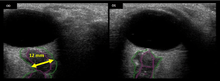

The astronauts afflicted with long term visual changes and prolonged intracranial hypertension have all been male, and SOS may explain this because in men, the sternocleidomastoid muscle is typically thicker than in women and may contribute to more compression. The reason that SOS does not occur in all individuals may be related to anatomic variations in the internal jugular vein. Ultrasound study has shown that in some individuals, the internal jugular vein is located in a more lateral position to Zone I compression, and therefore not as much compression will occur, allowing continued blood flow.